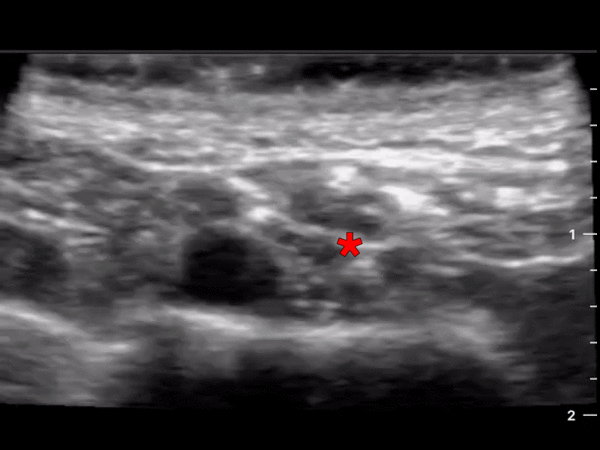

This is an ultrasound clip demonstrating the anatomy for a supraclavicular nerve block. The probe is placed parallel to and just superior to the clavicle. The subclavian artery can be seen pulsating in the middle of the screen just superior to the hyperechoic cortex of the first rib. The * denotes the large brachial plexus bundle which can be seen just lateral to the artery. Pleural sliding can also be appreciated on both sides of the rib. Michael Macias